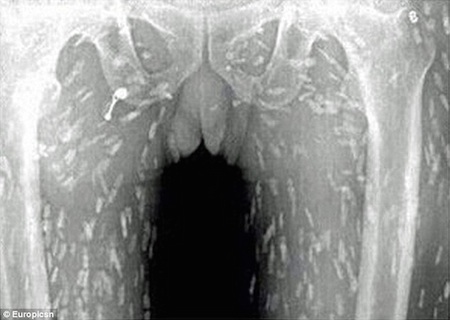

После того, как у него возникли поразительные симптомы, включая расстройство желудка и зудящую кожу, неудачный энтузиаст суши попал в больницу. В Народной больнице Гуанчжоу № 8 в провинции Гуандун он, наконец, получил лечение от заражения лейкемией. Инцидент, безусловно, один для книг, основанный на графических рентгеновских снимках ужасающей болезни. Хотя человек мог умереть от неудачного кризиса здоровья, он получил отличный уход из больницы, а затем выздоровел. Надеюсь, он в следующий раз пропустит сашими.

После того, как его отправили в больницу, выяснилось, что у него была паразитарная инфекция